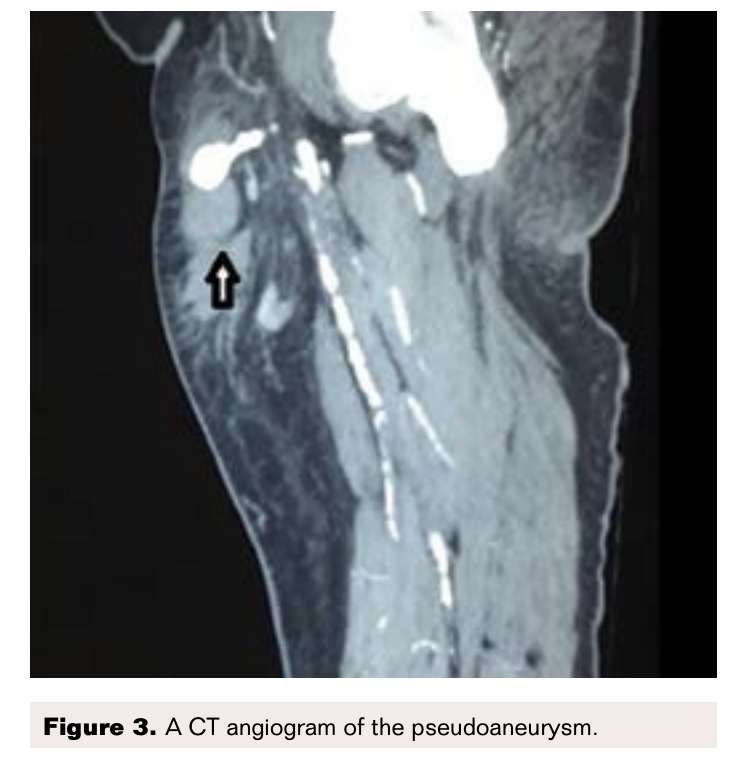

On the ultrasound arterial doppler a heterogeneously hyperechoic area was found at the upper part of the right thigh, with skin discoloration suggestive of a hematoma. This had a well-defined echogenic area with a Ying and Yang color flow, and swirling suggestive of a pseudoaneurysm. This appeared to arise from the common femoral artery (Figure 1). Since the swelling was very large, to enable further treatment decisions we sent the patient for a CT angiography of the thigh (Figures 2-5).

CT Angiogram Findings

A pseudoaneurysm arising from anterior aspect of the right common femoral artery (CFA) just above bifurcation was observed with a sac noted in the subcutaneous space that measured 1.9 x 1.4 cm. A tract from this sac had a length of 2.6 cm and arose from the CFA. A hematoma was noted in the anterior and medial aspect of the thigh in the subcutaneous space adjacent to the pseudoaneurysm (Figures 2-5).